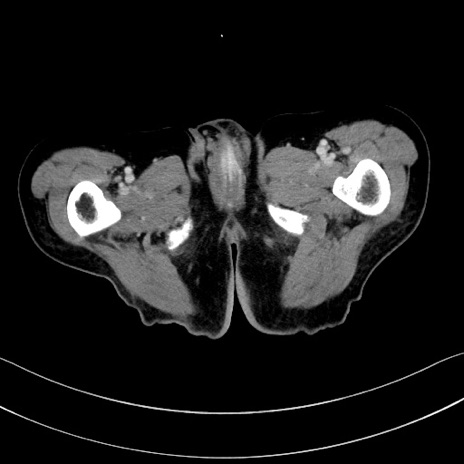

症例28(横断像)

【症例】60歳代男性

【現病歴】胃癌にて胃全摘後。食思不振が悪化し、夜中に嘔吐することがある。

【既往歴】胃癌、胃全摘、脾摘、胆摘後